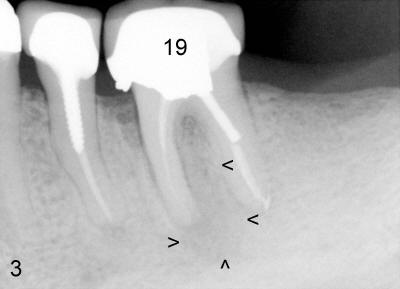

When attention was turned to the left side of this patient, chronic infection was noticed near the buccal furca of the tooth #19 (Fig.4: arrowhead). As a matter of fact, this type of infection has persisted for five years (Fig.3: arrowheads). Extraction of the tooth #19 has not been done because of mild and periodic discomfort. In contrast, signs and symptoms associated with the tooth #30 were more severe and acute, leading to extraction. Ideally, #19 should be extracted prior to or during #30 implant placement to prevent post-implant infection.